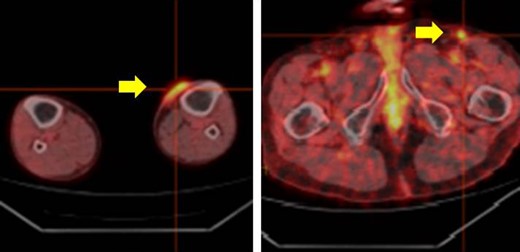

The whole body PET-CT (yellow arrow indicates accumulation of FDG).

The patient was an 83-year-old male with a granulomatous tumor on his left lower leg. He said that it had existed for about 10 years. An incisional skin biopsy was performed at a neighbor medical institution and histopathologically suggested PCACC. He was introduced to our out-patient clinic. At his admission, the tumor was about 4 cm in the diameter and showed a few red granulomatous nodules (Fig. 1). MRI revealed that the tumor infiltrated subcutaneous tissue but did not reach muscle and bone (Fig. 2). The whole-body PET-CT showed that fluorodeoxyglucose (FDG) accumulated at the tumor area of the left lower leg. FDG also accumulated in the left inguen, however any other accumulation was not defected (Fig. 3). Therefore, it was suspected that the left inguinal hot spot was the metastatic lesion from the PCACC lesion at the left lower leg. At the first operation, the tumor was resected 2 cm far from the tumor margin, including basal muscle fascia and periosteum, and the defect was covered with an artificial dermis under general anesthesia (Fig. 4). At the same time, inguinal lymph node dissection was performed. Histopathological examination of the tumor revealed that cubical cells which had high nuclear-to-cytoplasmic ratio proliferated with cribriform, tubular or cord-like structure in the dermis and subcutaneous tissue. Perineural invasion by the tumor was observed. Metastasis to superficial inguinal lymph node was also histological confirmed (Figs 5 and 6). Most lumens had mucus which was stained by Alcian-blue (AL-B) and Periodic acid-Schiff (PAS) inside of them (Fig. 7). In the immunohistochemical findings, the tumor cells were positive for EMA, SMA, S-100protein, BerEP4, p63 and C-kit (Fig. 8). According to these clinical and pathological findings, the tumor was finally diagnosed the tumor as PCACC. Microscopically, the tumor was resected completely.